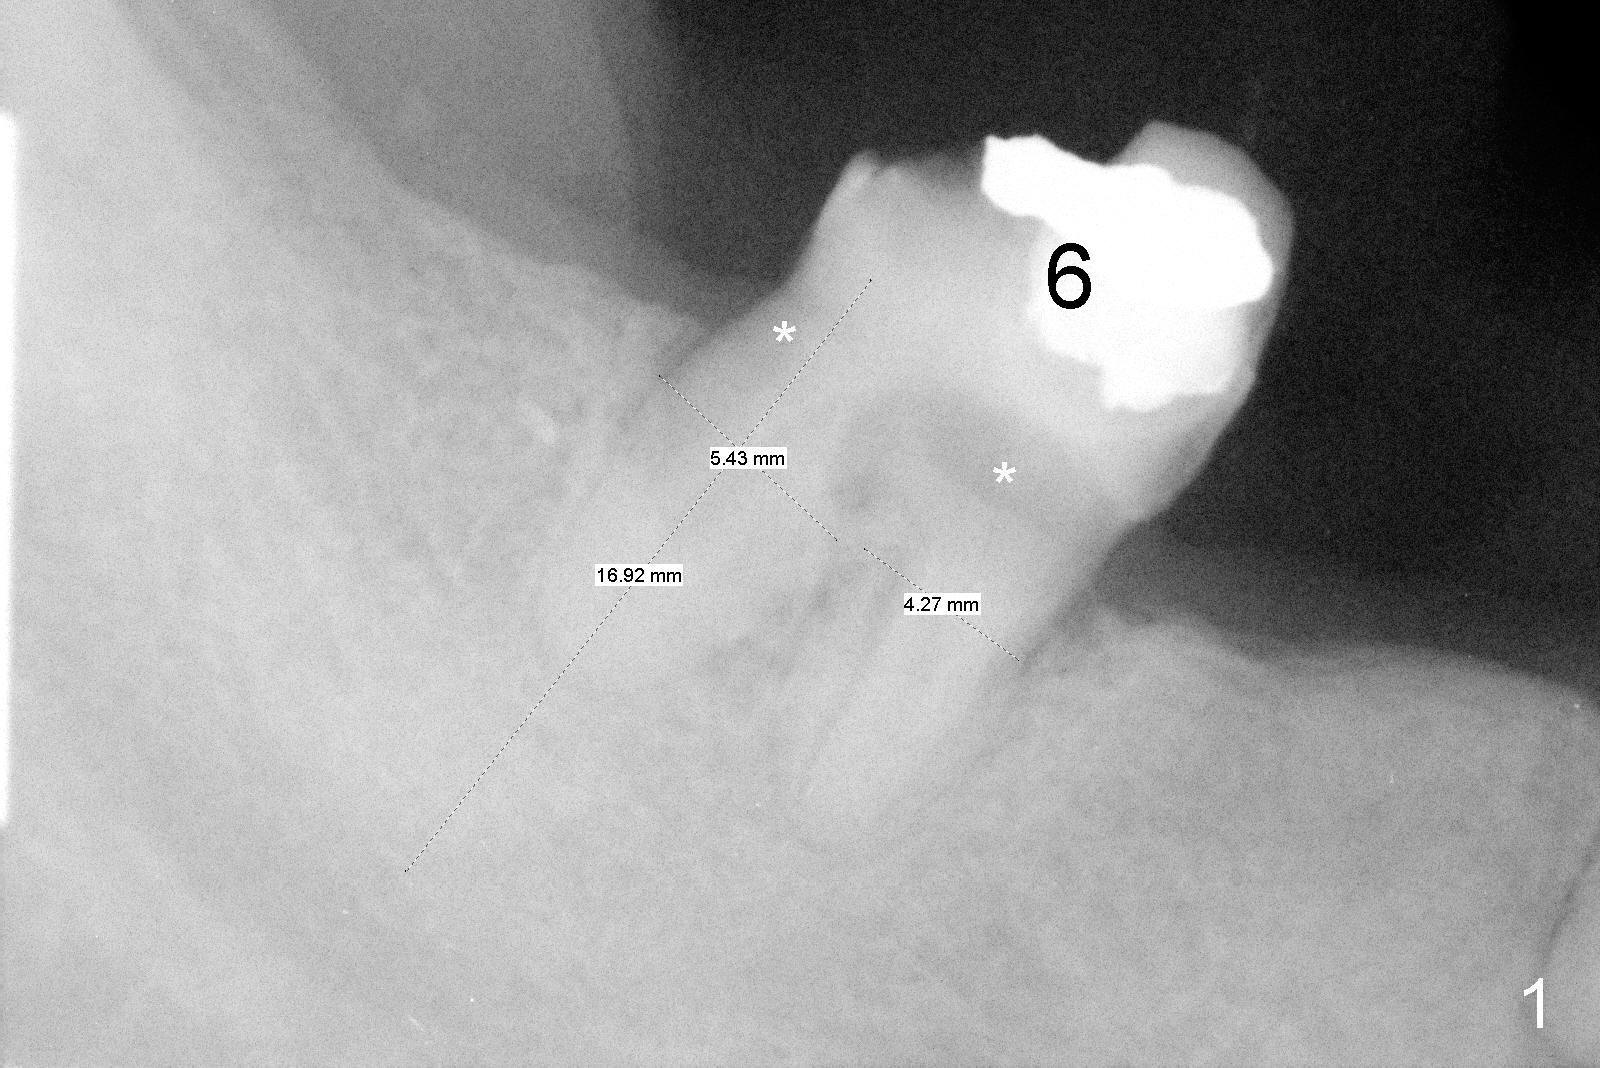

The lower right bridge (from canine (Fig.2: 3) to 1st molar (Fig.1: 6)) fails while a 77-year-old man is undergoing chemotherapy for urinary bladder cancer. The abutments of the bridge are extracted without plan for implants (Fig.4). Four months later, the patient returns for implants (Fig.3), but the ridge is narrow (Fig.5). While 2 of 3x14 mm 1-piece implant are placed at the canine and 1st bicuspid sites, 2 piece ones at the 2nd bicuspid and 1st molar sites (Fig.6: 3.5x11 mm, 5x14 mm). Soft (Fig.7-10) and hard (Fig.11) tissues heal 1 week (Fig.7) and 4 months (Fig.8-11). There is minimal bone resorption 1 year 7 months post cementation (Fig.12,13, non-splinting). It appears that narrow diameter implants are a valid solution to narrow ridge at the sites of the lower canine and premolar. As long as there are enough implants for function, the crowns are not necessary to be splinted. Surprisingly, the patient starts flossing after implant restoration. Retrospectively an immediate provisional bridge should have been fabricated.